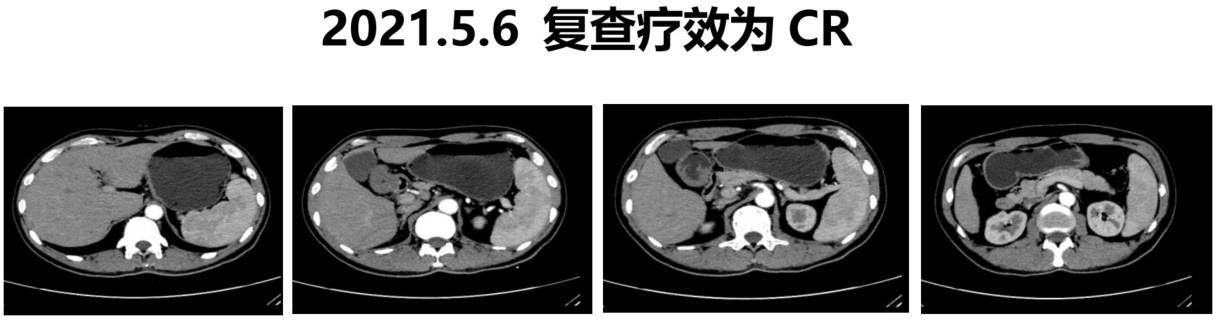

2021年2月7日,患者转为“卡培他滨+替雷利珠单抗”方案进行维持治疗,持续至2022年9月(免疫药物治疗两年后结束)。2021年5月,维持治疗期间复查增强CT显示:胃壁未见明显肿块,未见明显肿大淋巴结,疗效评估为完全缓解(CR)。